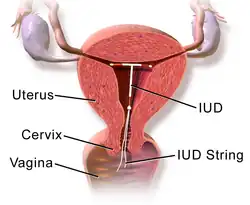

An intrauterine device (IUD), also known as an intrauterine contraceptive device (IUCD or ICD) or coil,[3] is a small, often T-shaped birth control device that is inserted into the uterus to prevent pregnancy. IUDs are a form of long-acting reversible contraception (LARC).[4]

Most copper IUDs have a T-shaped frame that is wound around with pure electrolytic copper wire and/or have copper collars (sleeves). The arms of the frame hold the IUD in place near the top of the uterus. The Paragard TCu 380a measures 32 mm (1.26") horizontally (top of the T), and 36 mm (1.42") vertically (leg of the T). Copper IUDs have a first-year failure rate ranging from 0.1 to 2.2%.[46] They work by damaging sperm and disrupting their motility so that they are not able to fertilize an egg. Specifically, copper acts as a spermicide within the uterus by increasing levels of copper ions, prostaglandins, and white blood cells within the uterine and tubal fluids.[6][47] The increased copper ions in the cervical mucus inhibit the sperm's motility and viability, preventing sperm from traveling through the cervical mucus, or destroying it as it passes through.[48] Copper can also alter the endometrial lining, and while studies show that this alteration can prevent implantation of a fertilized egg ("blastocyst"), it cannot disrupt one that has already been implanted.[49]

During the insertion procedure, health care providers use a speculum to find the cervix (the opening to the uterus), pinch the cervix to stabilize it open with a tenaculum,[74] and then use an insertion device to place the IUD in the uterus. The insertion device goes through the cervix. The procedure itself, if uncomplicated, should take no more than five to ten minutes.[75]

Generally, the removal is uncomplicated and reported to be not as painful as the insertion because no instrument needs to go through the cervix.[80] This process requires the health care provider to find the cervix with a speculum and then use ring forceps, which only go into the vagina, to grasp the IUD strings and then pull the IUD out.